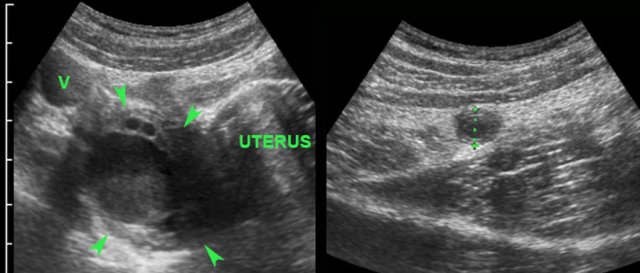

In this young woman, a conspicuous hemorrhagic right ovarian cyst (arrowheads) was visualized and held responsible for her RLQ symptoms.

Further searching however revealed acute appendicitis, the cyst being a confusing coincidental finding.